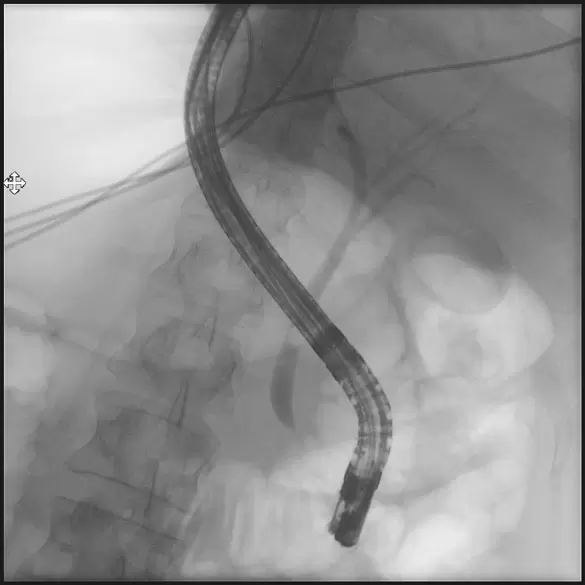

Bile duct depiction (ERCP)

ERCP (endoscopic retrograde cholangio-pancreatography) is a technique that combines the use of endoscopy and fluoroscopy to depict the biliary and pancreatic ductal systems. It is necessary for the diagnosis and treatment of gall stones and diseases of the pancreas. Through a special endoscope (side-view duodenoscope) a contrast agent is injected into the biliary and/or pancreatic ducts so they can be documented using X-rays. Gall stones can be removed by trawling the common bile duct with a basket. Constrictions and stenosis in the bile or pancreatic ducts can be bridged through insertion of a plastic- or self-expanding metall stent. This examination is always done under sedation and requires a short hospital stay.